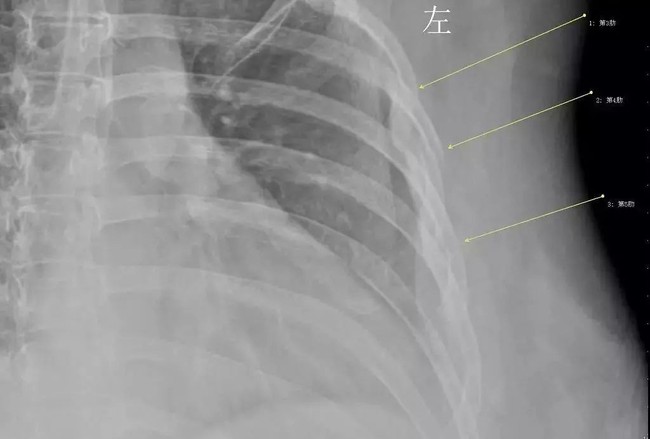

Sau một trận ho dữ dội, Hàn Tiếu đột nhiên bị khó thở, và đau ở phần ngực. Khi khám bệnh, kết quả khiến bác sĩ vô cùng sốc, tất cả xương sườn thứ 3, 4 và 5 của Hàn Tiếu đều bị gãy do chứng loãng xương sớm.

Theo báo cáo, bệnh nhân là Hàn Tiếu năm nay 30 tuổi, cô là nhân viên văn phòng của công ty nước ngoài. Gần đây, đến đợt rét tháng 3, Hàn Tiếu đột nhiên bị cảm lạnh. Sau một trận ho dữ dội, Hàn Tiếu đột nhiên bị khó thở, và đau ở phần ngực. Hàn Tiếu đã đến Khoa phẫu thuật lồng ngực của Bệnh viện trung tâm thành phố Vũ Hán để kiểm tra. Kết quả khiến bác sĩ vô cùng sốc, tất cả xương sườn thứ 3, 4 và 5 của Hàn Tiếu đều bị gãy.

Ba chiếc xương sườn bị gãy chỉ vì trận ho, điều này khiến Hàn Tiếu không thể tin nổi. Bác sĩ sau khi hỏi về lịch sử bệnh và thói quen sinh hoạt hàng ngày của cô thì phát hiện, Hàn Tiếu có thói quen uống cà phê thay nước, có ngày cô uống đến 10 cốc cà phê, thói quen này đã kéo dài được 7 năm.

Bác sĩ đã yêu cầu Hàn Tiếu làm kiểm tra mật độ xương, kết quả đúng như suy đoán của bác sĩ, tuổi xương của Hàn Tiếu tương đương với người 60 tuổi. Cô đã mắc chứng loãng xương sớm, bệnh này có liên quan lớn đến sở thích uống cà phê.